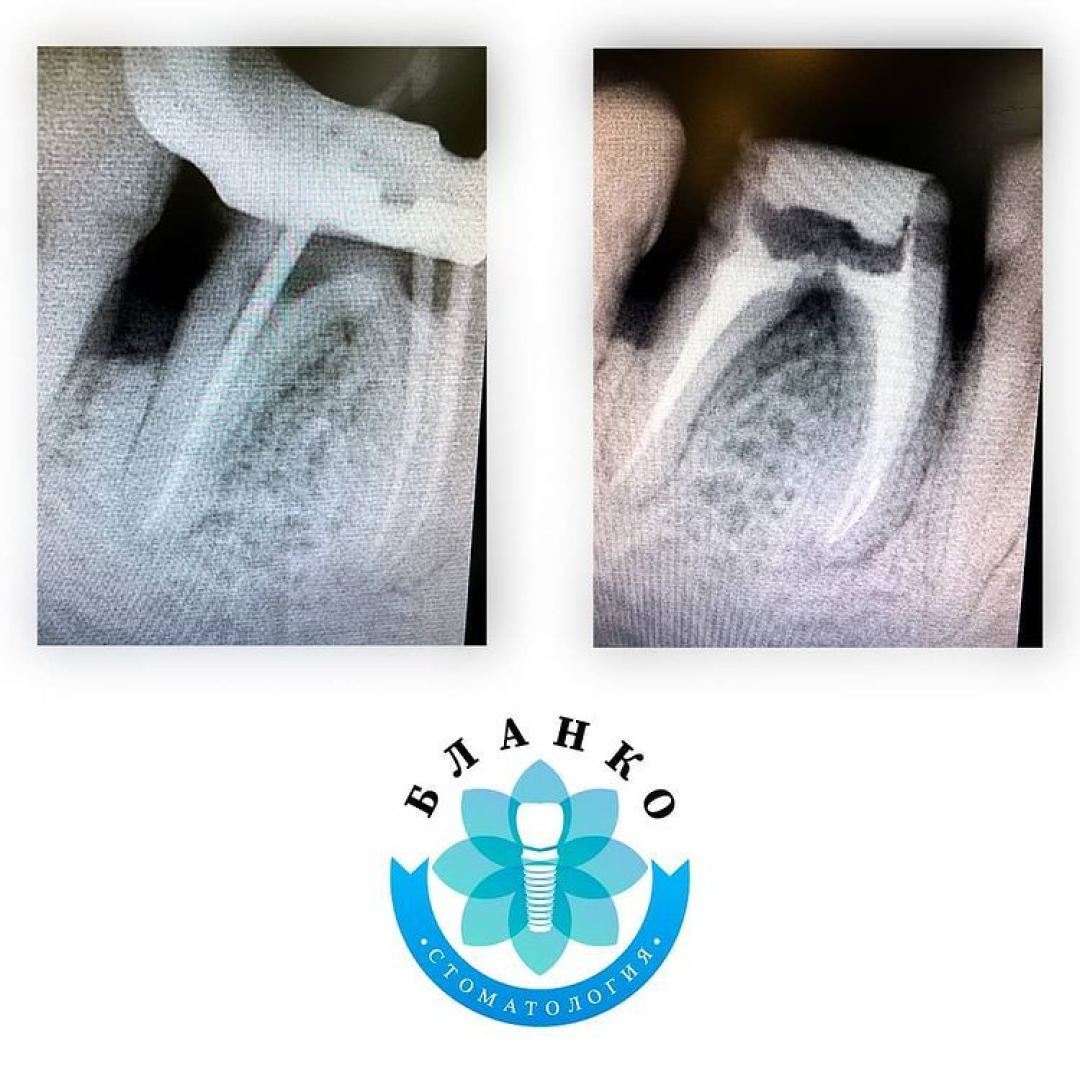

✳️На начальном снимке мы видим зуб 4.6 ( обведен красным цветом ),в котором наблюдается хроническое воспаление вокруг корней зуба и плохая реставрация из пломбировочного материала, которая давно отошла от тканей зуба и под которой развился вторичный кариес ( снимок №2 ).

✳️Чтобы такой зуб вытащить с того света была проделана огромная работа, которая видна на всех последующих снимках, а именно:

— убрана несостоятельная реставрация

— извлечены анкерные штифты

— распломбированы и пролечены корневые каналы

— запломбированы корневые каналы